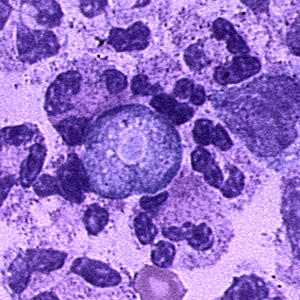

E. histolytica trophozoite

single nucleus with centrally placed karyosome. Cytoplasm contains ingested RBC’s.